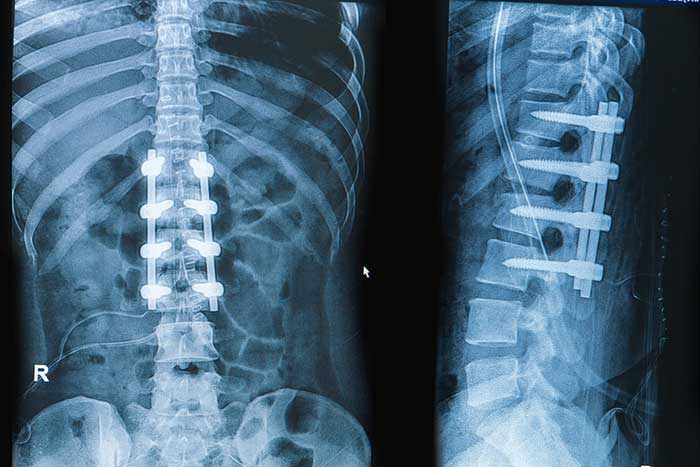

In spinal fusion, the surgeon permanently joins two or more spinal vertebrae. The joined vertebrae no longer have movement between them. As post-operative time passes, the fused vertebrae heal into a single solid bone.

The surgeon then installs rods and screws on the fused vertebrae to support the vertebrae with an internal cast.

Spinal fusion surgery, in comparison to less invasive implant techniques described below, has the benefits of better access to the spine for removal of damaged bone or discs. Spinal fusion surgery also offers greater visibility for placing the rods and screws and bone graft materials that stabilize the spinal bone.

- Device migration—Screws, plates, and rods implanted on the vertebrae could move and lead to complications and unforeseen after-effects.